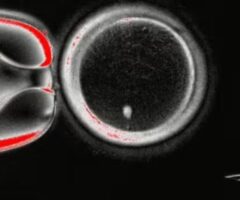

Όταν η ομάδα γονιμοποίησε το ωάριο με σπέρμα, αυτό άρχισε να αναπτύσσεται σε έμβρυο, μέχρι που το πείραμα σταμάτησε στην έκτη ημέρα – το χρονικό σημείο κατά το οποίο ένα έμβρυο θα μεταφερόταν στη μήτρα σε μια διαδικασία εξωσωματικής γονιμοποίησης (IVF).

Οι ερευνητές πέτυχαν αυτήν την εξέλιξη αφαιρώντας αρχικά τον πυρήνα από φυσιολογικά κύτταρα δέρματος και στη συνέχεια τον μετέφεραν σε ένα ωάριο δότη από το οποίο είχε επίσης αφαιρεθεί ο πυρήνας του.

Ωστόσο, ένα σημαντικό εμπόδιο ήταν το γεγονός ότι τα κύτταρα του δέρματος έχουν 46 χρωμοσώματα, ενώ τα ωάρια έχουν 23.

Για να το ξεπεράσουν αυτό, οι επιστήμονες κατάφεραν να αφαιρέσουν τα επιπλέον χρωμοσώματα χρησιμοποιώντας μια διαδικασία που ονομάζουν «μιτομείωση» (“mitomeiosis”).

Η διαδικασία αυτή, όπως εξήγησαν οι ερευνητές σε σχετική ανακοίνωση, «μιμείται τη φυσική κυτταρική διαίρεση και προκαλεί την απόρριψη ενός σετ χρωμοσωμάτων, αφήνοντας πίσω έναν λειτουργικό γαμέτη».